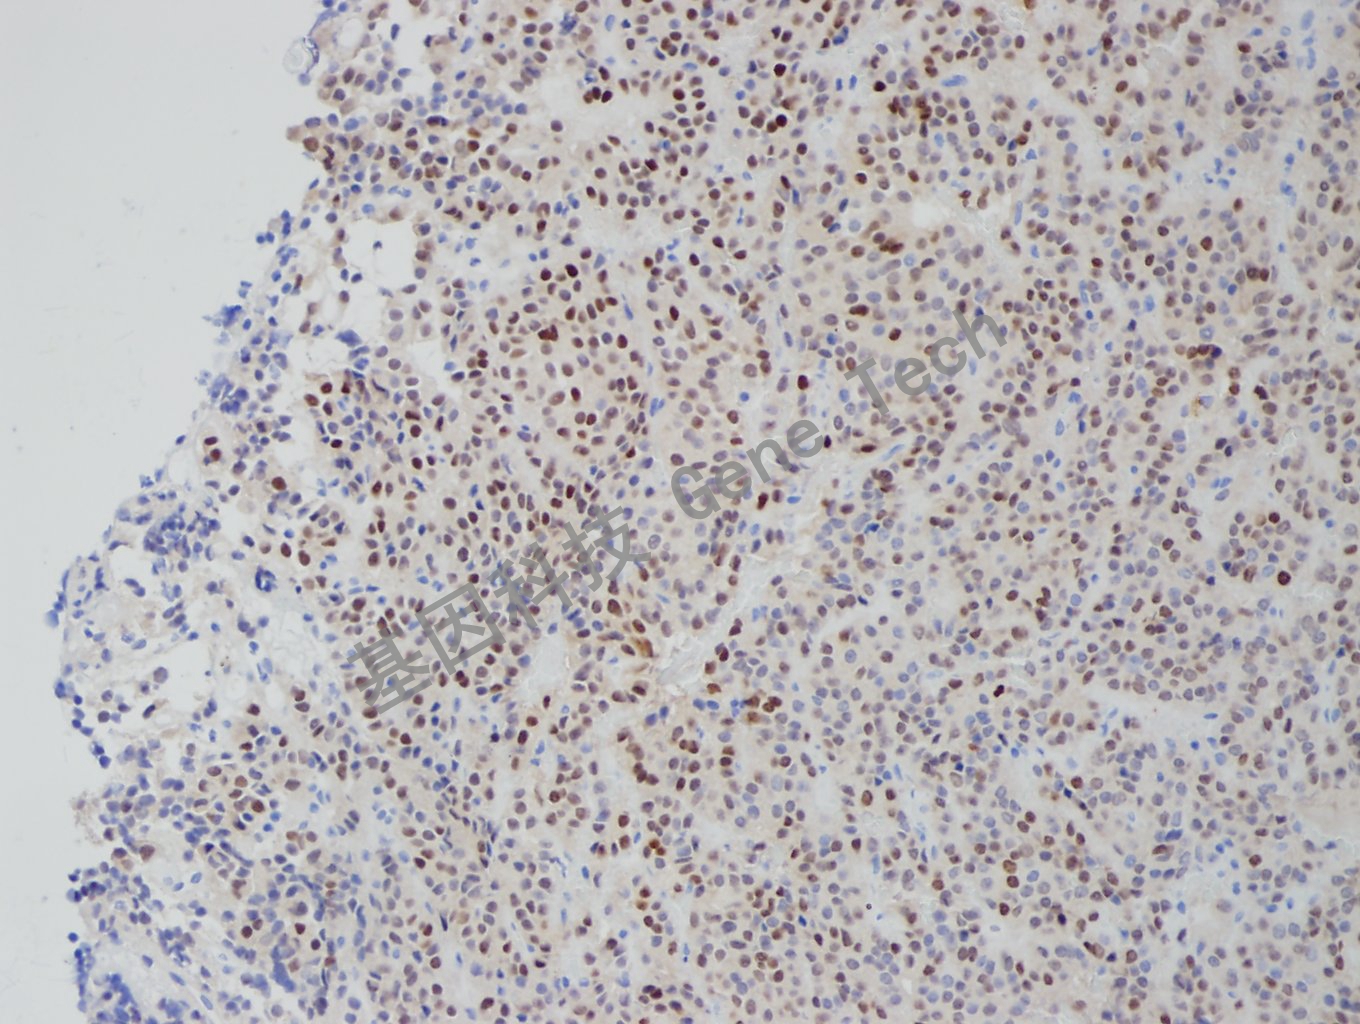

垂体瘤石蜡切片,用 T-Pit(GT2318)染色,细胞核阳性,DAB显色。